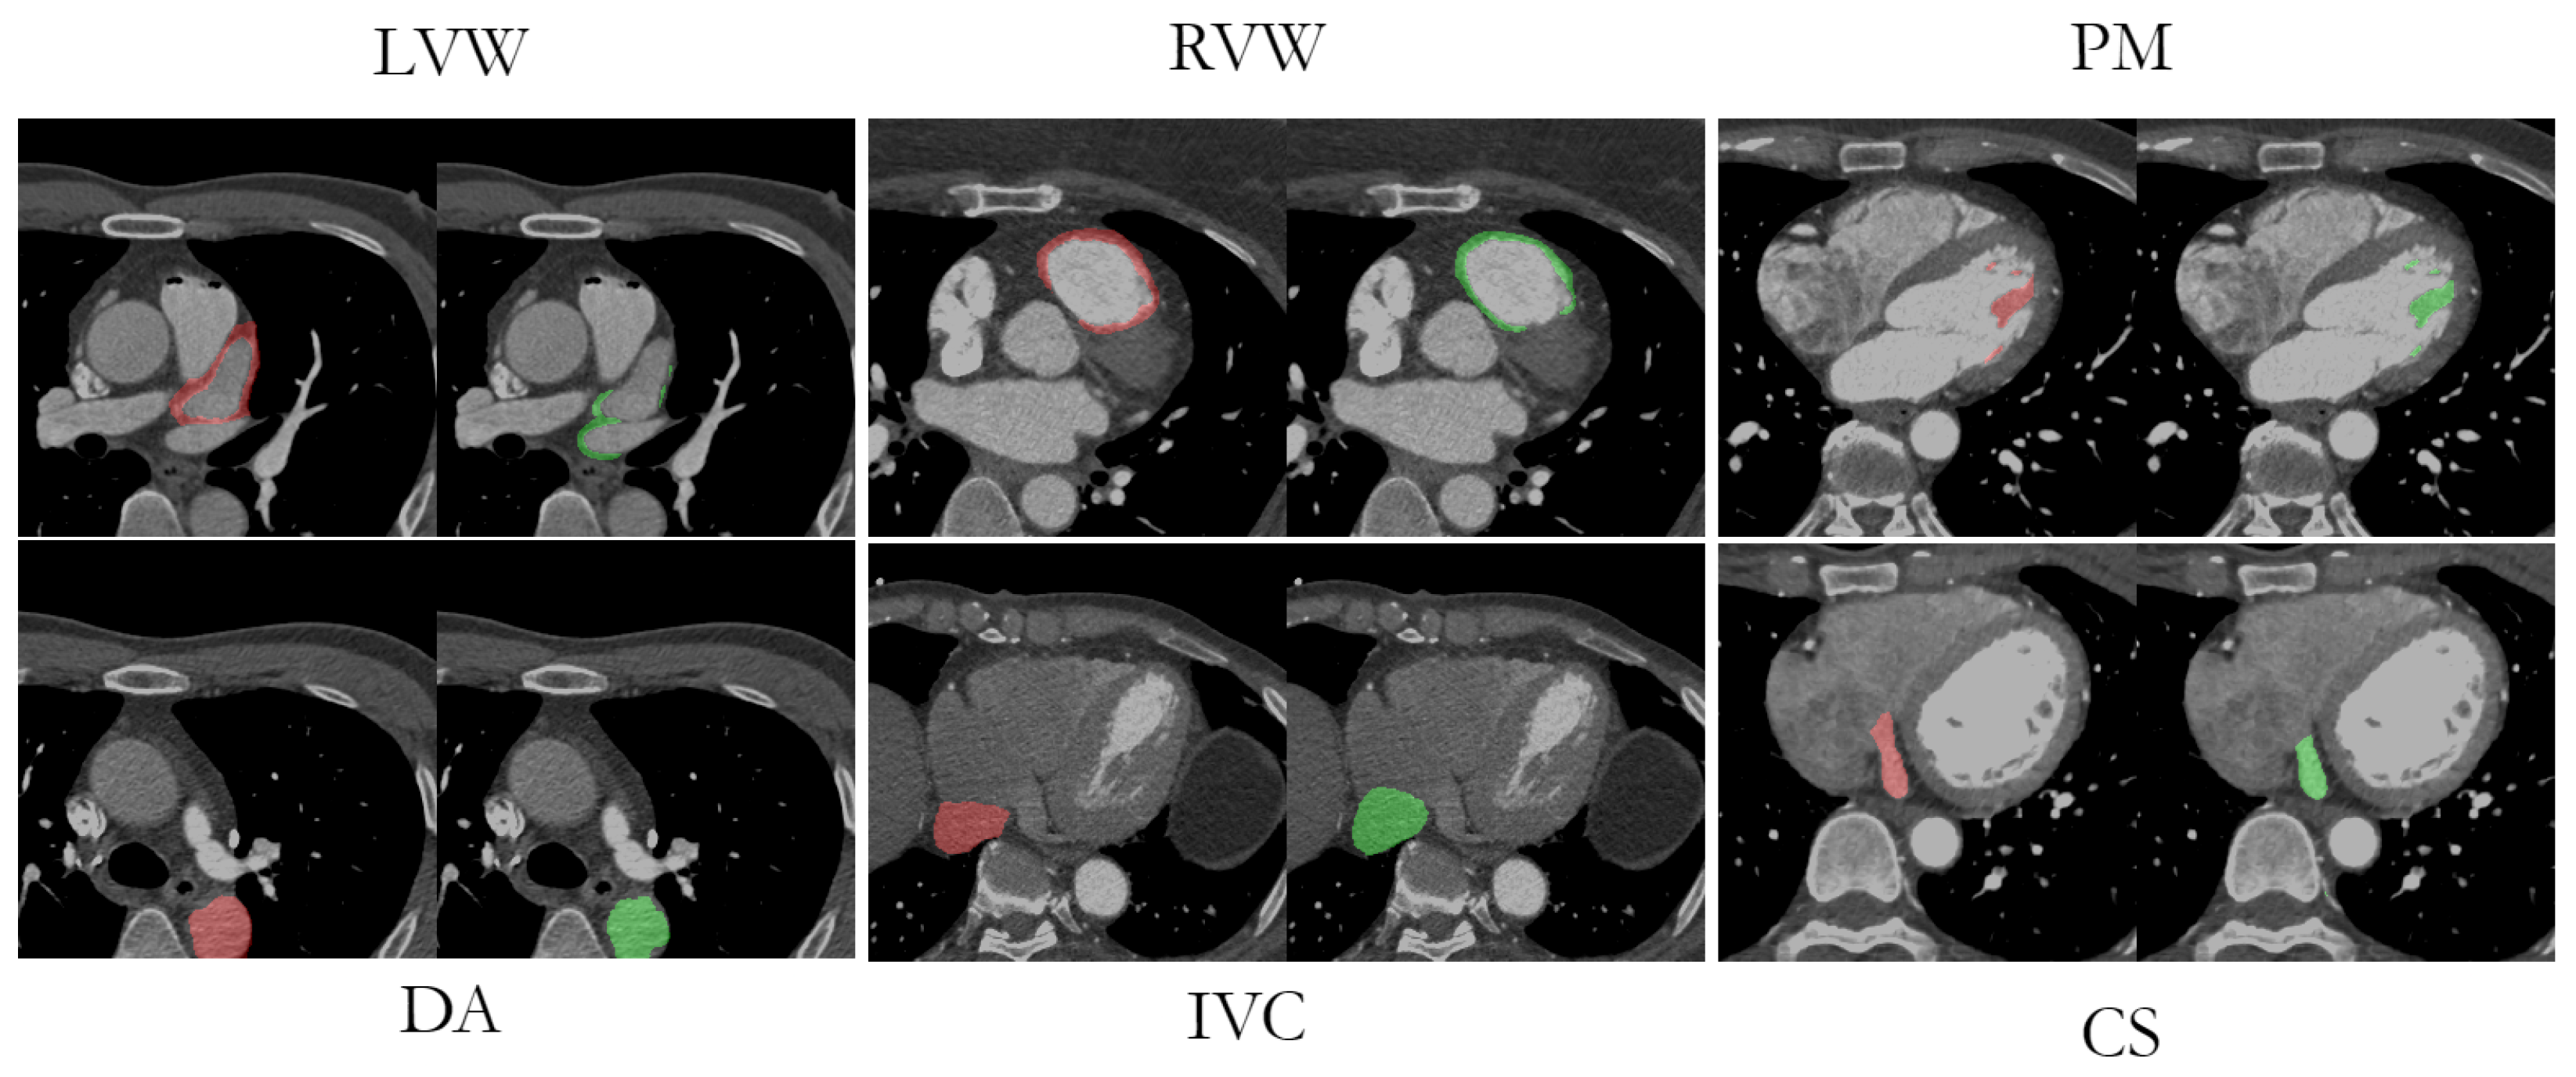

Visual comparisons between the original image, the manual labeling, and the AB-ResUNet+ model prediction are shown in Figure 8. The segmentation prediction examples and GT overlays over the original image for LVW, RVW, PM, DA, IVC, and CS more accurately illustrate the potential difficulties in segmentation due to low image quality, high and low contrast differences, and the highly anatomical complexity of the structures. The difficulty in identifying the irregularly shaped CS, especially with suboptimal contrast fluoroscopy, may account for the lower accuracy compared to the other vessels. The complex structure of LVWs and RVWs, which varies in different layers and in different patients, makes them a particular challenge for automatic segmentation methods.

Figure 8.

An example of original images from LVW, RVW, PM, DA, IVC, and CS dataset with an overlay of successful segmentation prediction (red) and corresponding GT (green).